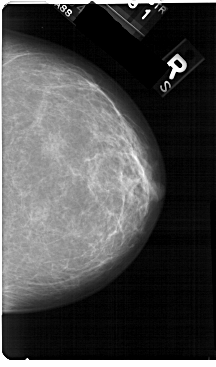

A_1323_1.RIGHT_CC

RIGHT_CC LINES 5491 PIXELS_PER_LINE 3226 BITS_PER_PIXEL 12 RESOLUTION 43.5 NON_OVERLAY